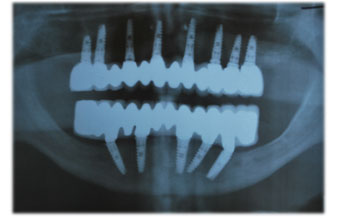

Our patient had severe problems and he was about to loose all of his teeths in the following one or two years. We have extracted all teeth and replaced 7 Implants per upper and lower part of the mouth and after one and a half months healing period, we have replaced the fixed porcelain prosthetics. During the healing period our patient was able to continue his normal life through the temporary prosthetis that we applied. Total treatment period was only three and half a months!

We have extracted all teeth and replaced 7 Implants per upper and lower part of the mouth and after a one and half month healing period we have replaced the fixed porcelain prosthetics. During the healing period our patient was able to continue her normal life through the temporary prosthetis that we had applied. Total treatment period was only four months.